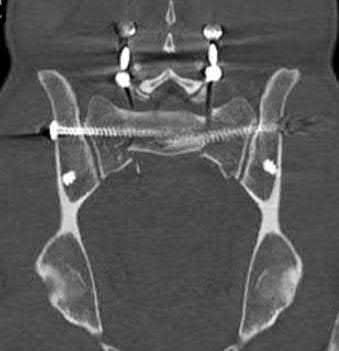

A 32-year-old male is involved in a high-speed motor vehicle collision and arrives with a unilateral C6-C7 facet dislocation and a dense C6 radiculopathy. Closed reduction with cranial tongs is attempted in the awake patient but is unsuccessful. What is the most appropriate next step in management?

In cases of cervical facet dislocation where awake closed reduction fails, or in a patient who cannot be examined (e.g., obtunded), an MRI of the cervical spine is the standard of care before proceeding to open reduction. The MRI is essential to identify the presence of a herniated intervertebral disc. If an anterior disc herniation is present, a posterior-only open reduction poses a significant risk of extruding the disc further into the spinal canal, potentially causing a catastrophic spinal cord injury. Therefore, MRI dictates whether an anterior approach (to remove the disc before reduction) is required.